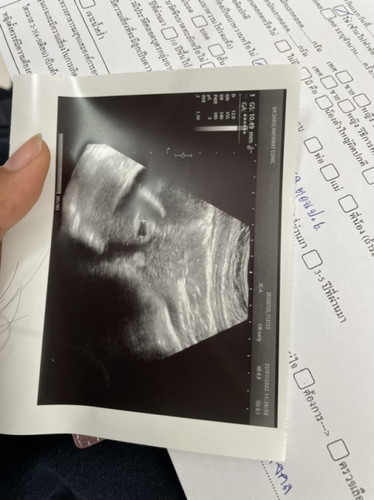

พึ่งไปอัลตราซาวด์มา

หมอบอกได้ประมาณ5สัปดาห์แต่ยังไม่เห็นตัวเด็กเลยค่ะ เสี่ยงเป็นท้องลมมั้ยคะ ตอนนี้กังวลมากๆเลยค่ะแม่ๆคนไหนเป็นแบบนี้บ้างคะ

มันเห็นแค่ถุงตั้งครรภ์ถ้าแค่5วีคค่ะ หมอบอกว่าอะไรบ้างคะตอนไปซาว

หมอให้ไปซาวอีกทีวันที่6ค่ะ เขาก็บอกว่าอาจมีความเสี่ยงบ้างค่ะ